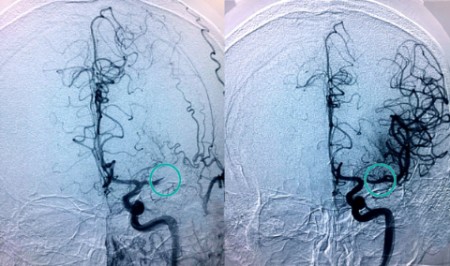

"Cuando una arteria del cerebro se obstruye se dispone de una ventana de muy poco tiempo para recanalizarla", explica el doctor Jaime González Valcárcel, neurólogo coordinador de la Unidad de Ictus del Complejo Hospitalario Ruber Juan Bravo. "Cada minuto cuenta en la fase aguda del ictus. Sabemos que por cada 15 minutos que se adelanta la primera intervención en caso de ictus disminuye un 4 por ciento el riesgo de discapacidad y también en un 4 por ciento la mortalidad".

La Unidad de Ictus de Quirónsalud en Madrid dispone de un sistema de telemedicina, denominado Teleictus, que permite que un neurólogo pueda ver durante las 24 horas del día a cualquier paciente con sospecha de ictus del Complejo Hospitalario Ruber Juan Bravo, Hospital Universitario Quirónsalud Madrid

. "El neurólogo de guardia del Complejo Hospitalario Ruber Juan Bravo puede acceder en tiempo real a la exploración del paciente y a sus pruebas del resto de centros, pudiendo ser tratado el paciente en un primer momento o trasladarlo para ser intervenido y extraer el trombo si fuera necesario", detalla el doctor Rafael Arroyo.